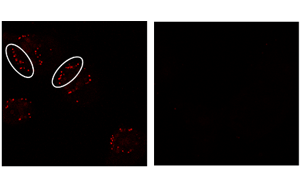

免疫細胞能夠像嗅探犬一樣檢測感染,使用一種叫做Toll樣受體的特殊傳感器,簡稱TLRs。但是是什么信號激活了TLRs,這種激活的規(guī)模和性質(zhì)與被檢測到的物質(zhì)之間有什么關(guān)系?在最近的一項研究中,來自波恩大學(xué)和波恩大學(xué)醫(yī)院(UKB)的研究人員使用了一種創(chuàng)新的方法來回答這些問題。他們采用的方法可能有助于加快尋找對抗傳染病、癌癥、糖尿病或癡呆癥的藥物。